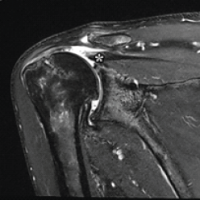

On clinical suspicion, ultrasound (USG) of the right elbow was done which showed a cystic lesion with thick internal echoes in the extensor and lateral aspect of the distal forearm measuring 3.6 × 1.3 × 2.8 cm with an approximal volume of 7.5 cc communicating with the elbow joint. MRI of the right elbow (Fig. 3) showed joint effusion with focal periarticular marrow edema in the proximal ulna concerning for inflammatory/infective arthritis.

Figure 3: Magnetic resonance imaging report of the right elbow joint.